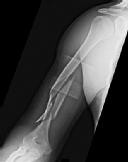

Question 9:

A 72-year-old female on prolonged bisphosphonate therapy presents with thigh pain. Radiographs show a fracture of the femoral shaft. Which of the following radiographic features is most characteristic of an atypical femur fracture associated with bisphosphonate use?

Correct Answer: Transverse or short oblique fracture line originating at the lateral cortex with localized periosteal thickening (beaking)

Explanation:

Atypical femur fractures (AFFs) associated with prolonged bisphosphonate therapy have specific major criteria defined by the ASBMR. These include a location anywhere from just distal to the lesser trochanter to just proximal to the supracondylar flare, transverse or short oblique orientation, non-comminuted (or minimally comminuted), and originating at the lateral cortex with localized periosteal or endosteal thickening ('beaking').